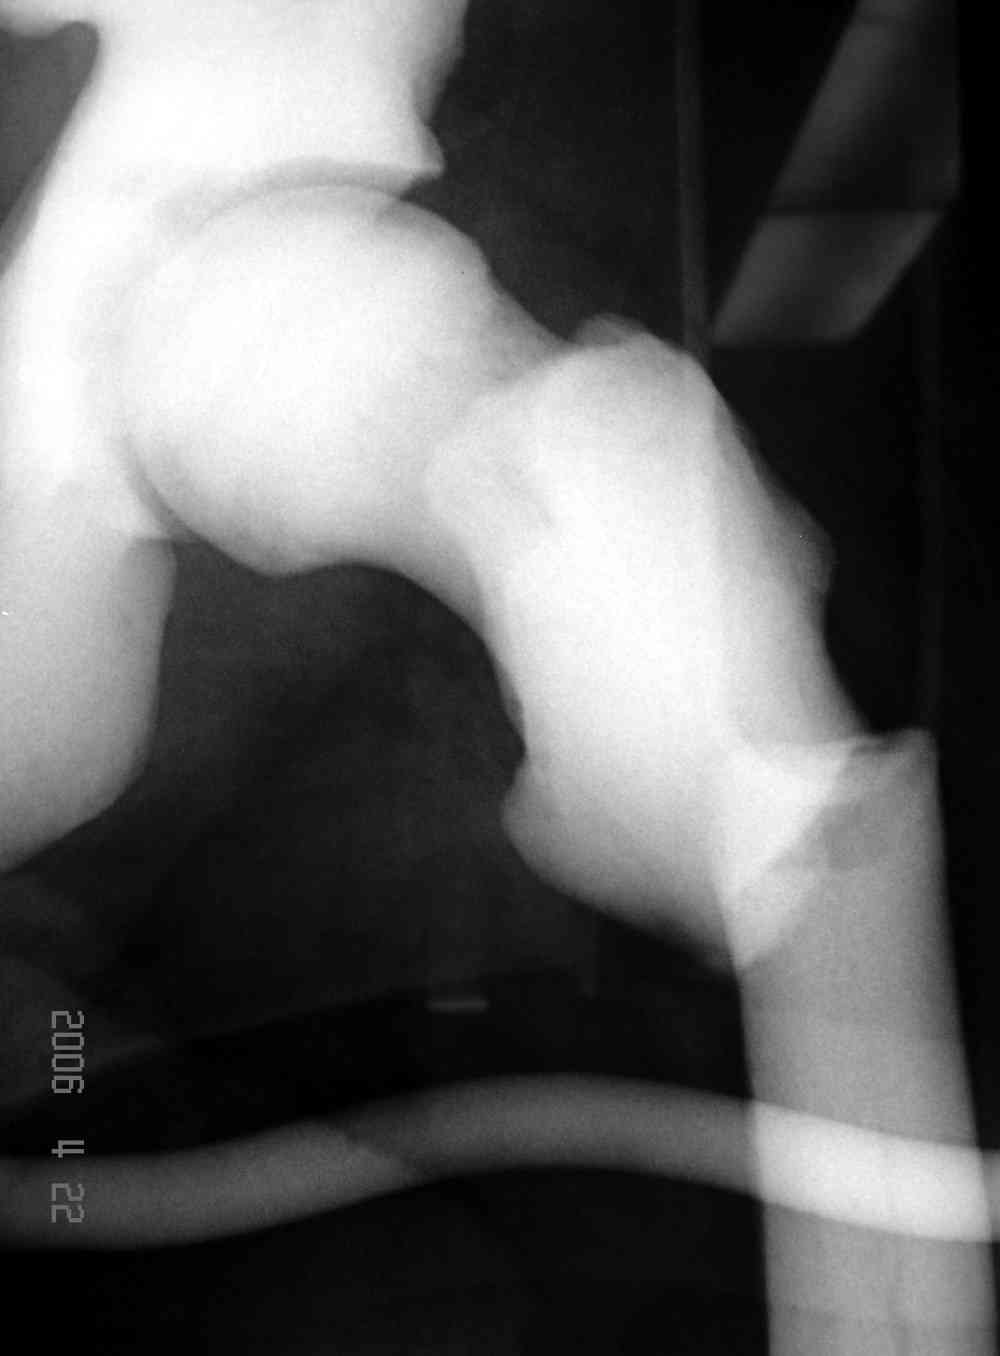

После неудачной попытки скелетного вытяжения в первом мед.учреждении, после осмотра снимков и изучения истории, поставили диагноз “Остеопетроз” или мраморная болезнь, редкая наследственная костная паталогия, где имеется нарушение формации остеокластов.

Не вызывает ли подозрение, что отсутствует медуллярный канал, как просверлить канал?

Канал, возможно, действительно запаян. Но разве большие проблемы его создать и рассверлить (если только это мраморная болезн?) Уверен, в вашей клинике есть для этого всё.